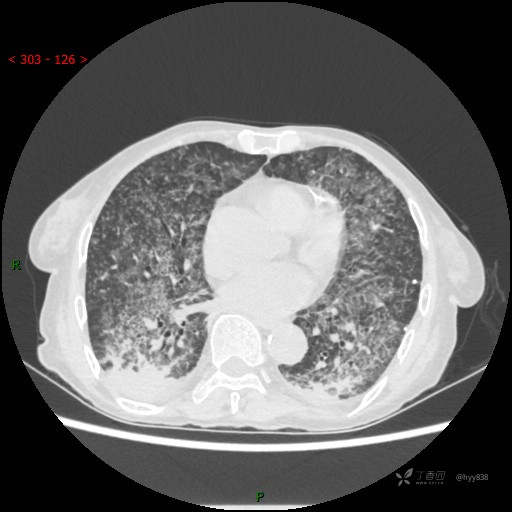

肺部弥漫性、疑难病变,感染或肿瘤?一元论或二元论?贴贴精彩---结果公布~

简要病史:患者10余天劳累后出现发热,最高体温达39.5℃,无畏寒、寒战、鼻塞、流涕,无头晕、头痛,无心慌、胸闷、胸痛,无咳嗽、咳痰、气喘,无反酸、烧心、恶心呕吐,无腹痛、腹胀等不适,于2022-5-31至当地中医医院住院治疗,诊断为重症肺炎,予以抗感染、抗病毒等对症支持治疗,仍反复发热,现为求进一步诊治,至我院门诊就诊,门诊以“重症肺炎”收入我科。 起病以来,患者精神、饮食、睡眠差,大小便正常,体力下降,体重无明显变化。

临床诊断:重症肺炎

胸部CT平扫